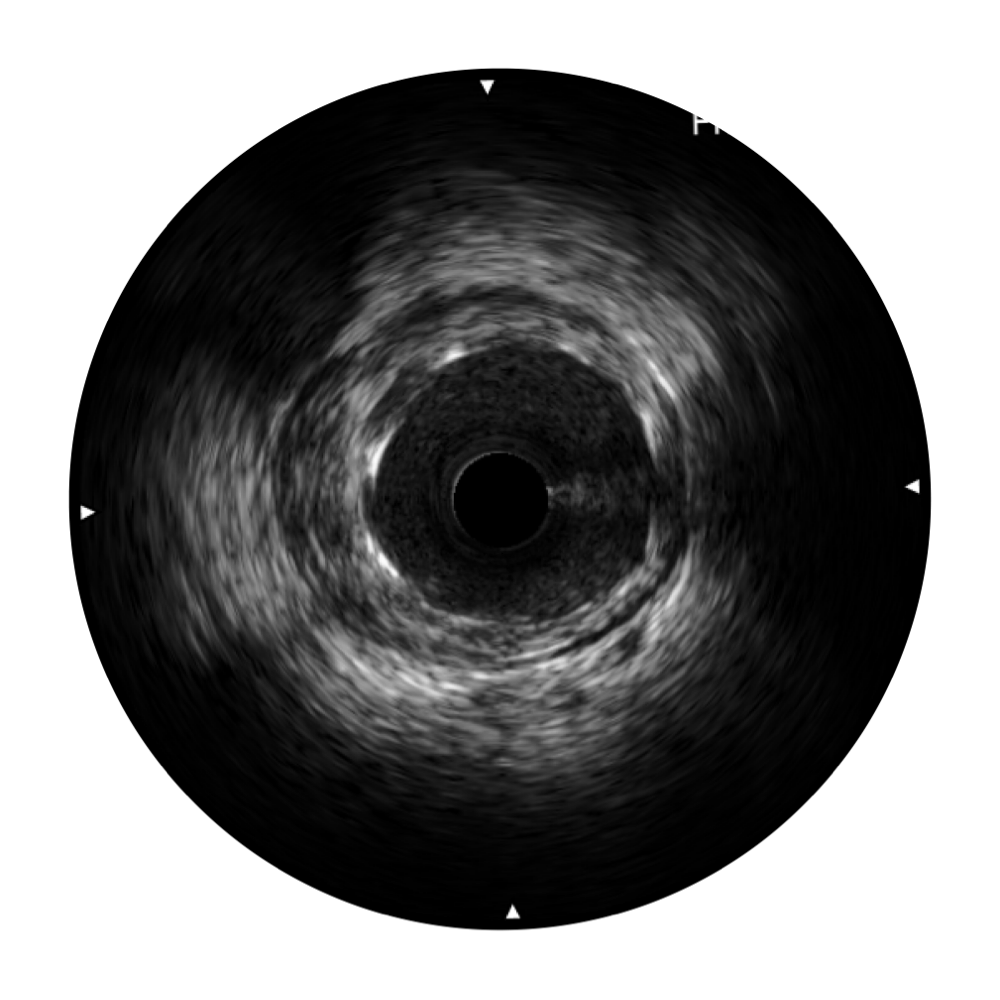

• milan米兰宽频IVUS图像

对比传统IVUS导管成像,milan米兰宽频IVUS图像的近场支架梁显影更细腻,远场中膜外血管仍清晰可辨,兼顾远中近,兼顾分辨力与穿透深度